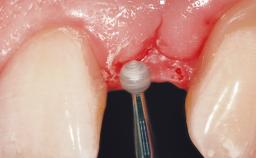

A 33-year-old female patient presented with an upper left central incisor that required extraction after a failed endodontic therapy. The tooth had been traumatized when the patient was a teenager and had undergone several endodontic treatments, including two apicectomy procedures. The patient was in good health and did not smoke. Clinical examination showed that the patient had a high lip line. In full smile, the gingival margins of the upper teeth were visible to the first molars. The gingival margins of central incisors 11 and 21 were only just showing. Examination of tooth 21 confirmed that the tooth was mobile and had hypererupted by 1 mm.

Lip Line No exposure of papillae Exposure of papillae Full exposure of mucosa margin

Periodontal Phenotype Low-scalloped, thick Medium-scalloped, medium-thick High-scalloped, thin

Soft Tissue Contour and Volume Slightly compromised